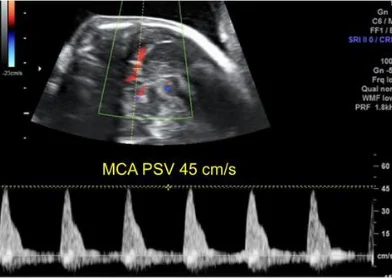

Hội chứng thiếu máu – đa hồng cầu Song thai (Twin Anemia-Polycythemia Sequence - TAPS)